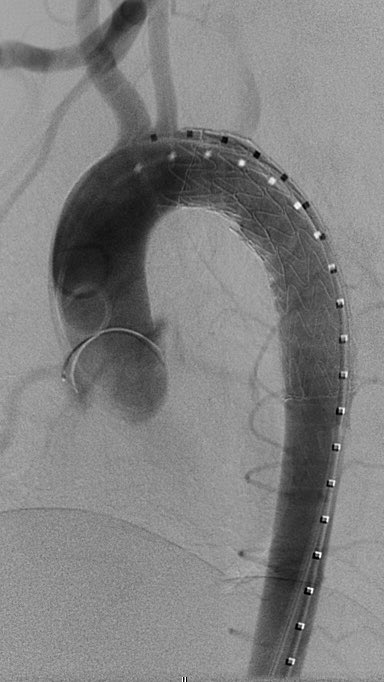

Blunt aortic injury (BAI) & repair. Heneghan et al suggest simplified SVS grading criteria based on tx differences. Thoughts? Minimal=nonoperative. Moderate=semielective TEVAR. Severe=emergency TEVAR. (J Vasc Surg 2016;64:171-6.) SIR RFS Society of Interventional Radiology JVIR

Blunt aortic injury (BAI) &amp; repair. Heneghan et al suggest simplified SVS grading criteria based on tx differences. Thoughts? Minimal=nonoperative. Moderate=semielective TEVAR. Severe=emergency TEVAR. (J Vasc Surg 2016;64:171-6.) <a href="/SIRRFS/">SIR RFS</a> <a href="/SIRspecialists/">Society of Interventional Radiology</a> <a href="/JVIRmedia/">JVIR</a>